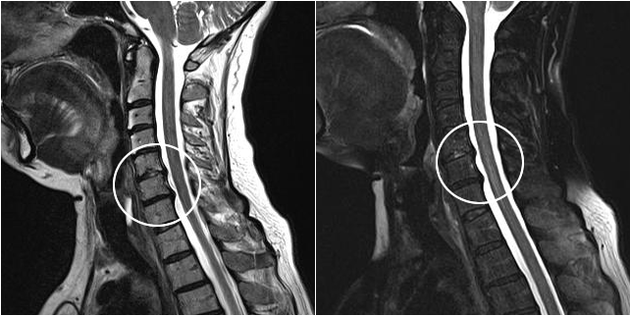

Mūsdienu diagnostikas metodes ietver MRI un CT, kas ļauj visprecīzāk pārbaudīt skrimšļa un kaulu audu iznīcināšanas procesus. Tāpat, izmantojot šo paņēmienu, ir ērti diagnosticēt trūces un citus mīksto audu defektus slimības avota tuvumā.